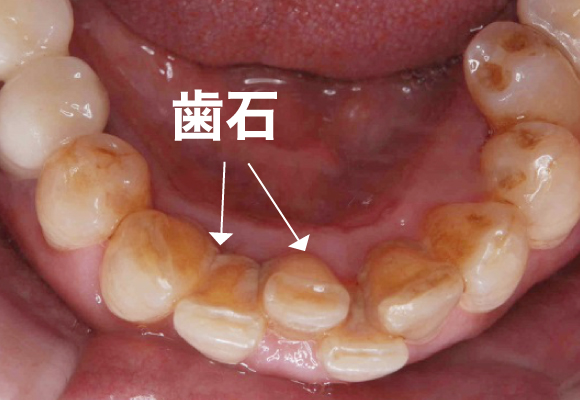

■プラークが固まって歯に頑丈にこびりついたものを歯石といいます。

歯磨きをしやすいように大まかな歯石を取る

歯茎と歯の境目に隠れた歯石を細かく取る